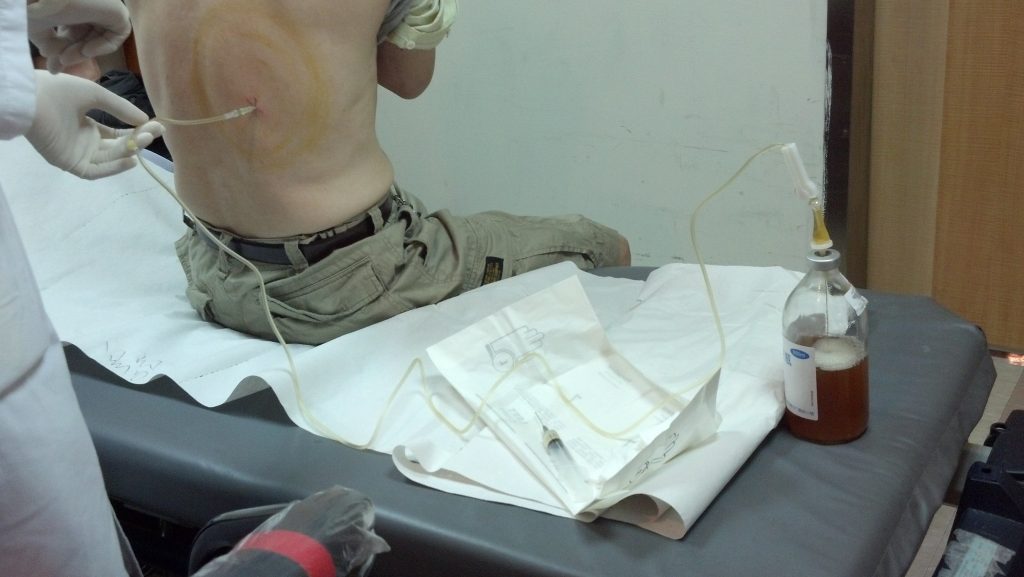

فغر الصدر الأنبوبي

يُقوم الطبيب المختص بعمل شقًا صغيرًا بجدار الصدر، ومن ثم يضع أنبوبًا بلاستيكيًا في التجويف الجنبي ويتركه عدة أيام.

تصريف الارتشاح

ولتصريف الارتشاح يضع الطبيب قسطرة طويلة الأمد عبر الجلد، وذلك في حال استمرار حدوث الارتشاح، وقد يستمر المريض بعمل التصريف في المنزل واتباع تعليمات من الطبيب بشأن متى وكيف يفعل ذلك؟.